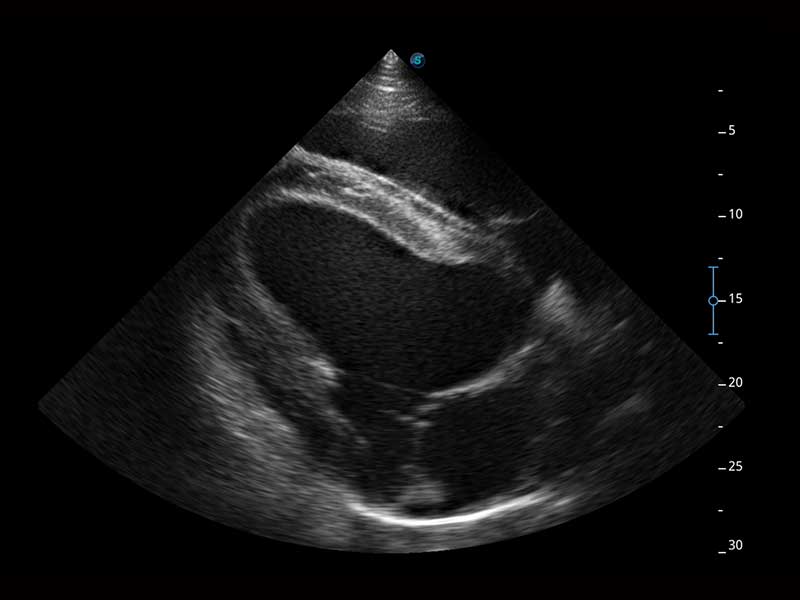

Az X Series Vet platform egy laptop kialakítású színes Doppler ultrahangrendszer, amely kiemelkedő képalkotó technológiáival van felszerelve, és professzionális állatorvosi szoftvereket kínál a kis kedvtelésből tartott állatoktól a nagy haszonállatokig. Kristálytiszta képalkotása és gördülékeny munkafolyamata új, továbbfejlesztett vizsgálati élményt biztosít, amely a magabiztos diagnózishoz szükséges pontosságot nyújtja.

Mivel az X Series Vet a SonoScape legújabb képalkotó technológiáit alkalmazza a nagy felbontású és mély penetrációjú képek előállításához, nagy mennyiségű diagnosztikai információ jeleníthető meg az ultrahang képernyőn. A továbbfejlesztett képminőség gyorsabb és pontosabb vizsgálatokat tesz lehetővé bármely állatfaj esetén.

A hatékonyságot, egyszerűséget és sokoldalúságot ötvözve az X Series Vet kiváló választás lógyógyászati vizsgálatokhoz. Speciális transzducerekkel és ló specifikus szoftverekkel felszerelve könnyedén készít lenyűgöző képeket az olyan alapvető alkalmazási területeken, mint az MSK, a reproduktív szervek vizsgálata, valamint a megfelelő penetrációt biztosítja hasi és kardiológiai vizsgálatokhoz is.